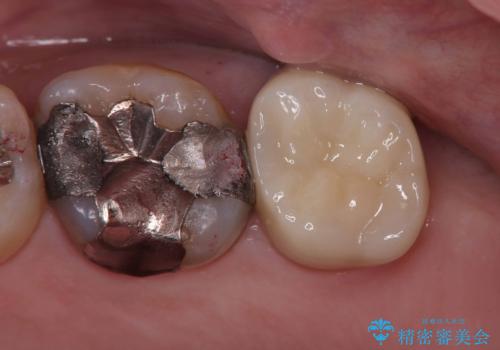

術前に神経の部分壊死と診断しましたが、神経をあけたときに出血が一切無かったので神経が死んでいるという診断は正しかったという事になります。

神経の処置にはマイクロスコープを使用しながら唾液を根管内に入れないようにラバーダムシートを使用しながら治療を行っています。

神経が死んでしまった原因はプラスチック(保険適用治療)の被せ物が劣化し歯と被せ物の間に生じた隙間からのリークが原因だと考えます。